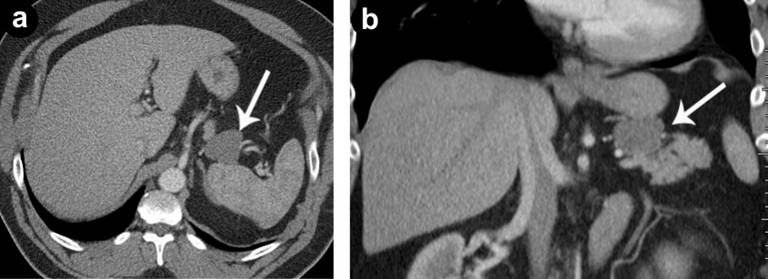

Various radiologic investigations were used in the pre-operative evaluation of the lesions. Imaging studies included CT scans, MRI and endoscopic ultrasound (EUS). All lesions were exophytic with one cyst originating from the head of the pancreas, two from the body, and three from the tail region. One patient had papillary projections into the lesion. Multiphase enhanced CT scan of the abdomen typically revealed a well-defined hypodense mass with imperceptible walls and Hounsfield units in the range of 15-20 (Figures 1 and 2). MRI of the abdomen was performed in one case and again showed a well-circumscribed exophytic lesion of the body of the pancreas with high T1 signal intensity, intermediate T2 signal intensity, with no enhancement following intravenous contrast administration (Figure 3). magnetic resonance cholangiopancreatography (MRCP) sequences did not show any continuity with the ductal system.

Figure 1. A 47-year-old male, with incidental pancreatic mass discovered on chest CT (Case #3). Axial (a.) and coronal (b.) venous phase CT show a well defined mass (arrows) arising off the superior aspect of the pancreatic body, measuring just above fluid attenuation. |